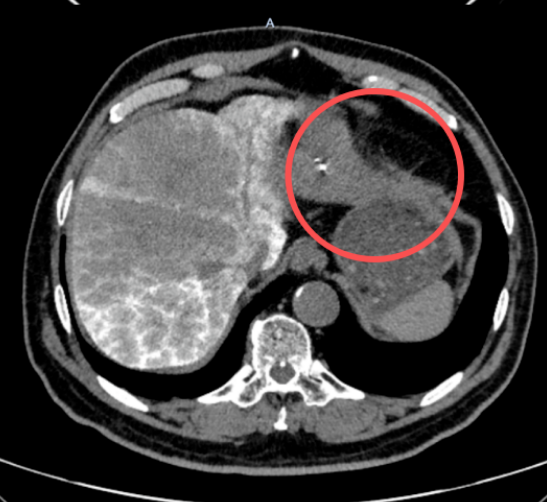

患者杨某(化名)体检中发现肝脏恶性病灶,大小达90*78mm。面对突如其来的病情,杨某及家属辗转多家医院后,慕名来到长春国文医院介入治疗科寻求治疗。

经系统治疗后,患者杨某身体状况逐步好转,不适症状缓解。近期复查显示,肝脏肿瘤病灶已从90*78mm缩小至29*16mm,病灶体积缩减,病情得到理想控制。拿到复查结果时,患者及家属难掩激动,对介入治疗科医护团队连连致谢。